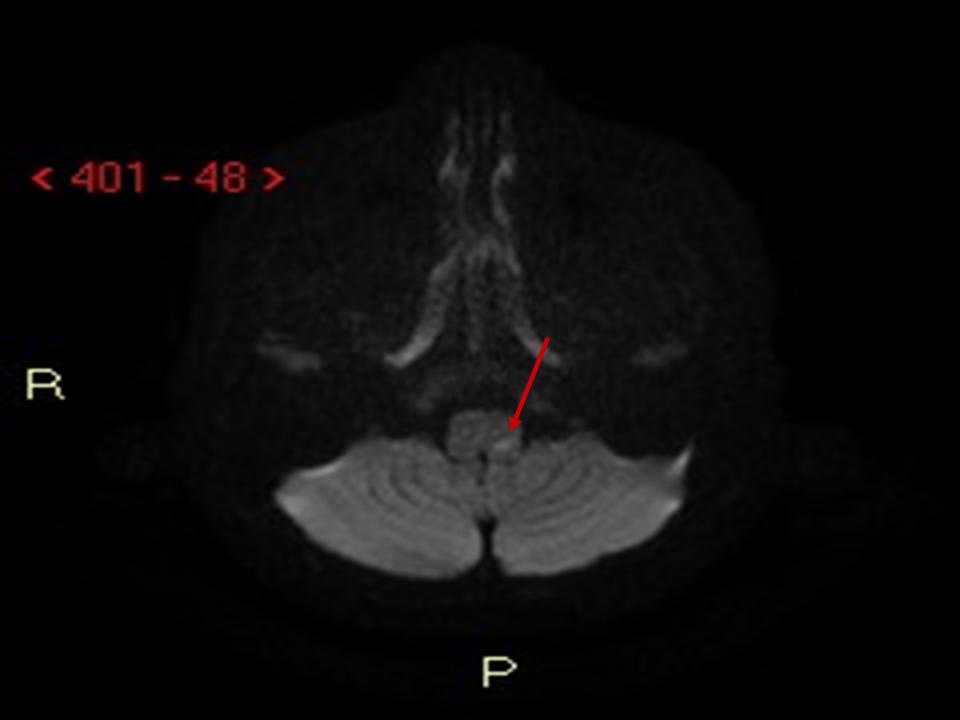

Figura

1. RMN. Assiale FLAIR (a sinistra): piccola lesione iperintensa a carico della porzione posteriore sinistra del bulbo compatibile con piccola lesione ischemica recente. DWI b1000 (a destra): piccola lesione a carico della porzione posteriore sinistra del bulbo con diffusione ristretta compatibile con piccola lesione ischemica recente.